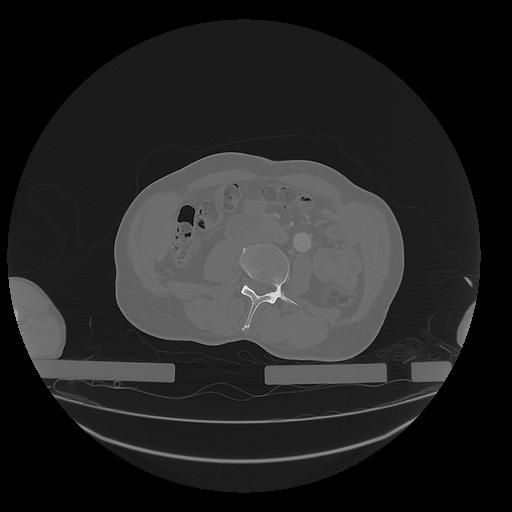

31 PULMON,CE,Vol,1.0,PULMON,,